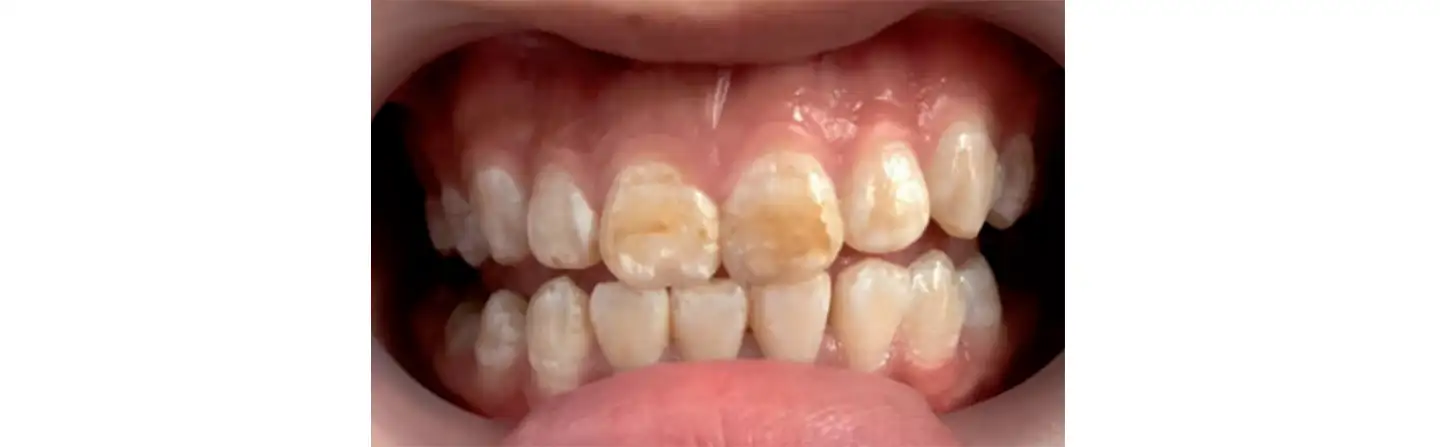

Пациентка 22 лет жалуется на эстетические дефекты в виде неровных меловых и коричневых пятен. Она живет рядом с угледобывающим заводом – источником фтора в воде и воздухе. Гигиена рта надлежащая, признаков гингивита не обнаружено.

Поставлен диагноз флюороз.

Клиническая картина до лечения